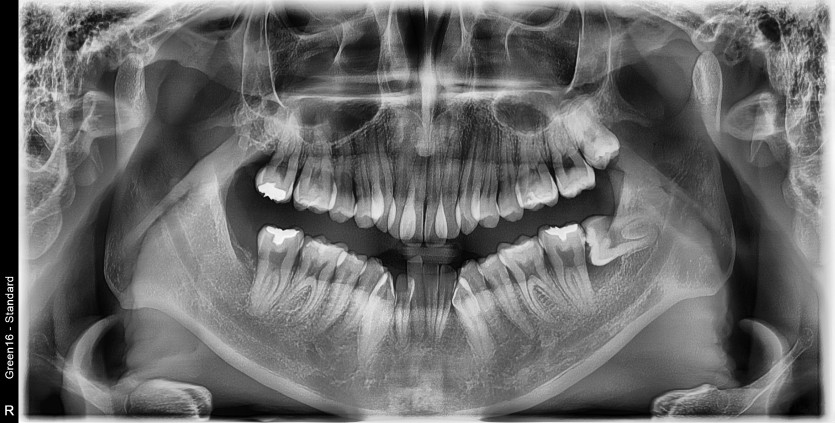

#28,38 사랑니 발치

구강외과 전문의가 당일 발치했습니다.